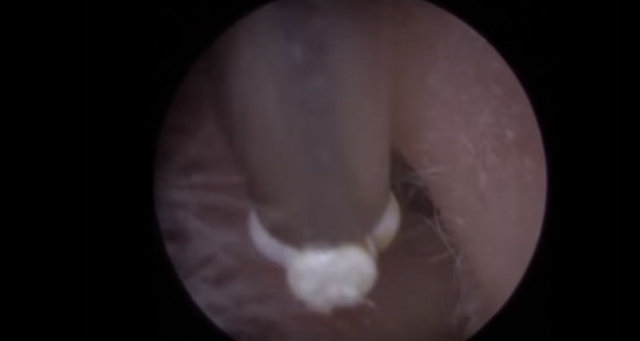

Kulağından 22 tane nesne çıkarılan adam hayrete düşürdü. İşin garip yanı ise kulağının içinden çıkan şeylerin işitme cihazı olmasıydı...